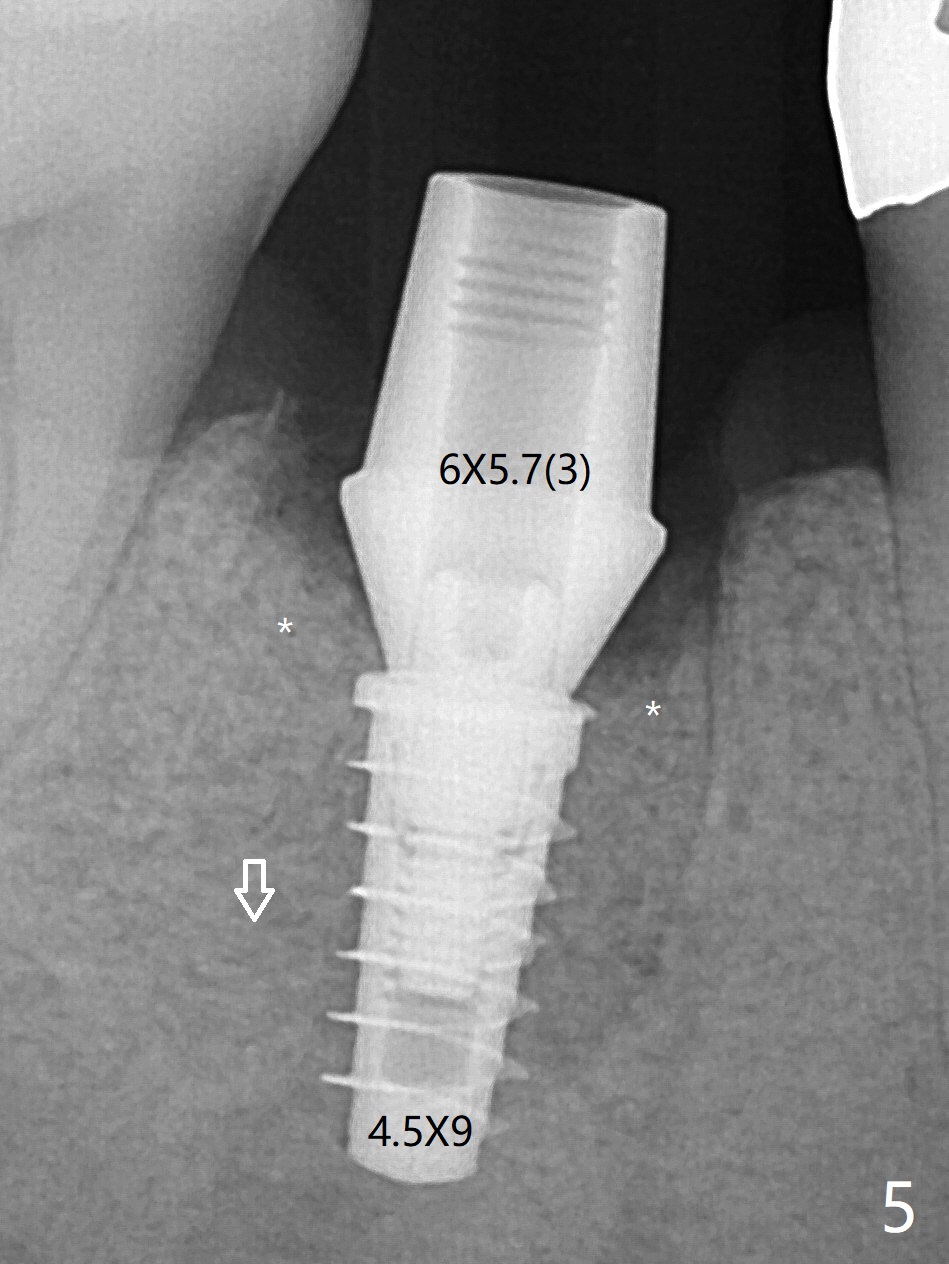

As planned, the crown of the tooth #30 with lingual (Fig.1 L) caries is removed and flattened with surgical handpiece so that the guide is able to be seated without interference. The osteotomy by 10.5 mm offset bone trimmer is lingual (Fig.2 white circle; due to in part the lingual caries and in part design error); in order to let the osteotomy to bounce back buccal, the part of the buccal roots are removed by surgical bur (arrows). The initial osteotomy by 2.2 mm drill is in the middle of the septum (Fig.3). After the last drill (3.5x11.5), the remaining roots are easily removed with proximators; a 4x11 mm dummy implant is placed with low stability and supracrestal lingual (Fig.4). Therefore a 4.5x9 mm final implant is placed with low torque. Following 4x11.5 mm drill, the torque increases to 20 Ncm. With insertion of healing screw, sticky bone (Fig.4 *: .5-1 mm cortical/cancellous allograft) is heavily packed around the implant (arrow), which apparently allows removal of the healing screw and placement of a 6x5.7(3) mm pair abutment without loosening the underlying implant. More bone graft is placed (Fig.6), followed by 2 pieces of PRF membranes. Although the implant is slightly buccally placed (Fig.7, due to over-removal of the buccal root, Fig.2 arrows), it is placed in the septum (Fig.8 S). To further compensate for the low implant stability, setting acrylic is applied in the edentulous area, particularly into the undercuts of the neighboring teeth (Fig.9 *) and around the abutment. The lingual margin of the acrylic dressing is extended (Fig.10 arrow) to cover the soft tissue defect associated with the lingual caries. As compared to the design (4x10 mm, Fig.11), the implant (4.5x9 mm, Fig.12) is placed buccal and ~ 2 mm deeper, reducing the chance of periimplantitis. The acrylic dressing is in place, but has mobility. The gingiva is healthy 2 weeks postop. The dressing is removed 1 month postop; the socket heals around the abutment buccal (Fig.13) and lingual (Fig.14). In spite of the immediate provisional, the abutment margin is substantially subgingival mesial 4 months postop, extremely difficult to take impression. A smaller diameter and longer cuff abutment is placed (Fig.15). The lingual gingiva heals normal 5 months postop, immediately before cementation (Fig.16).